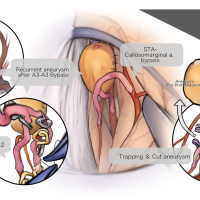

FEN2022シリーズ